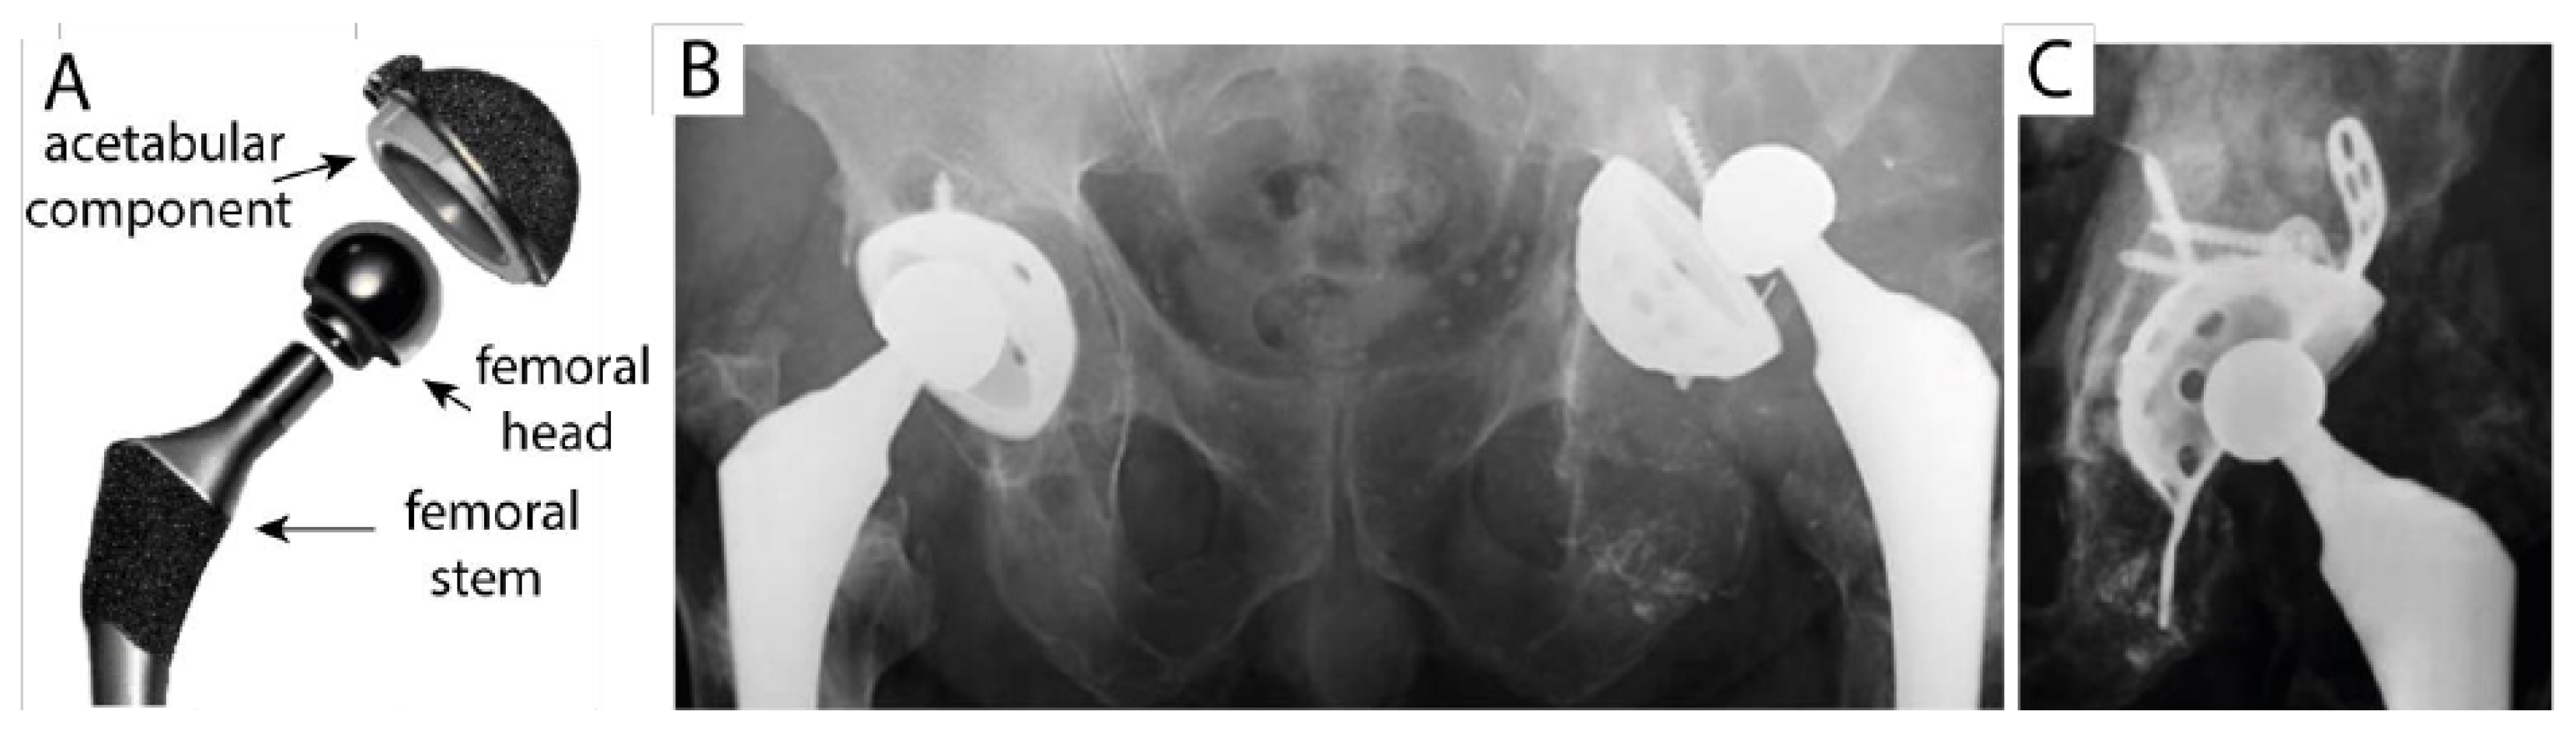

2. Evolution of Bone Implant Materials and Ceramics for Osseous Applications

3. Design and Challenges Associated with the Acetabular Cup